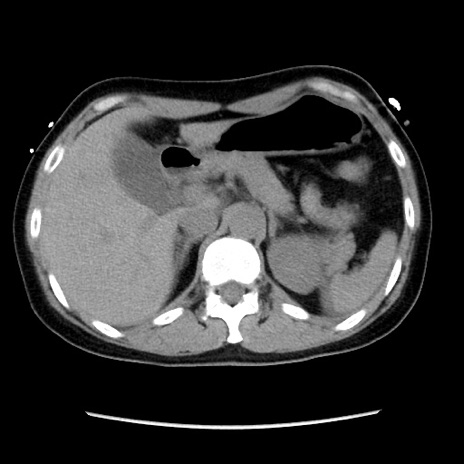

症例10(横断像)

【症例】 50歳代女性

【主訴】 腹痛

【現病歴】前日生レバーを食べた。今朝に排便あり。 昼前に突然発症の腹痛を生じ、当院救急外来を受診した。

【身体所見】 意識清明、腹部:平坦、軟、下腹部やや左を中心に圧痛・反跳痛あり、筋性防御あり

【データ】WBC 7800、CRP 0.07